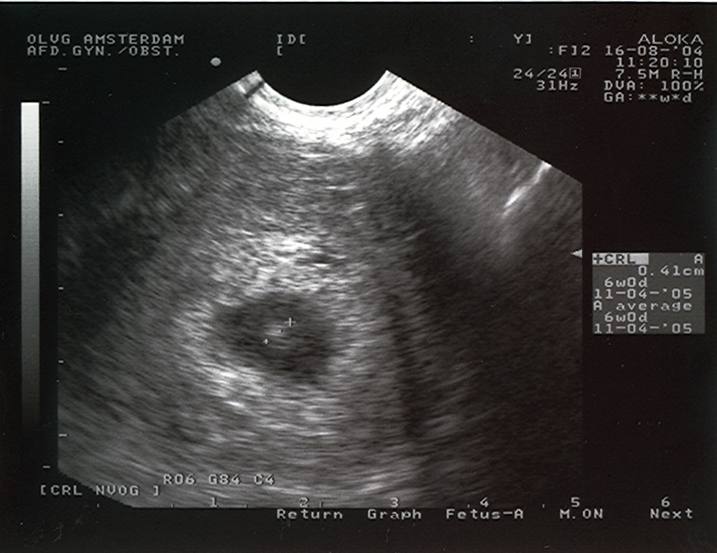

Ultrasound at 28 days

Ultrasound picture of a 4-week old pregnancy. On the right you can read the size: 0,41 cm. This means that the mother is about 12 days over time. If a pregnancy like this is unwanted, we can end it…